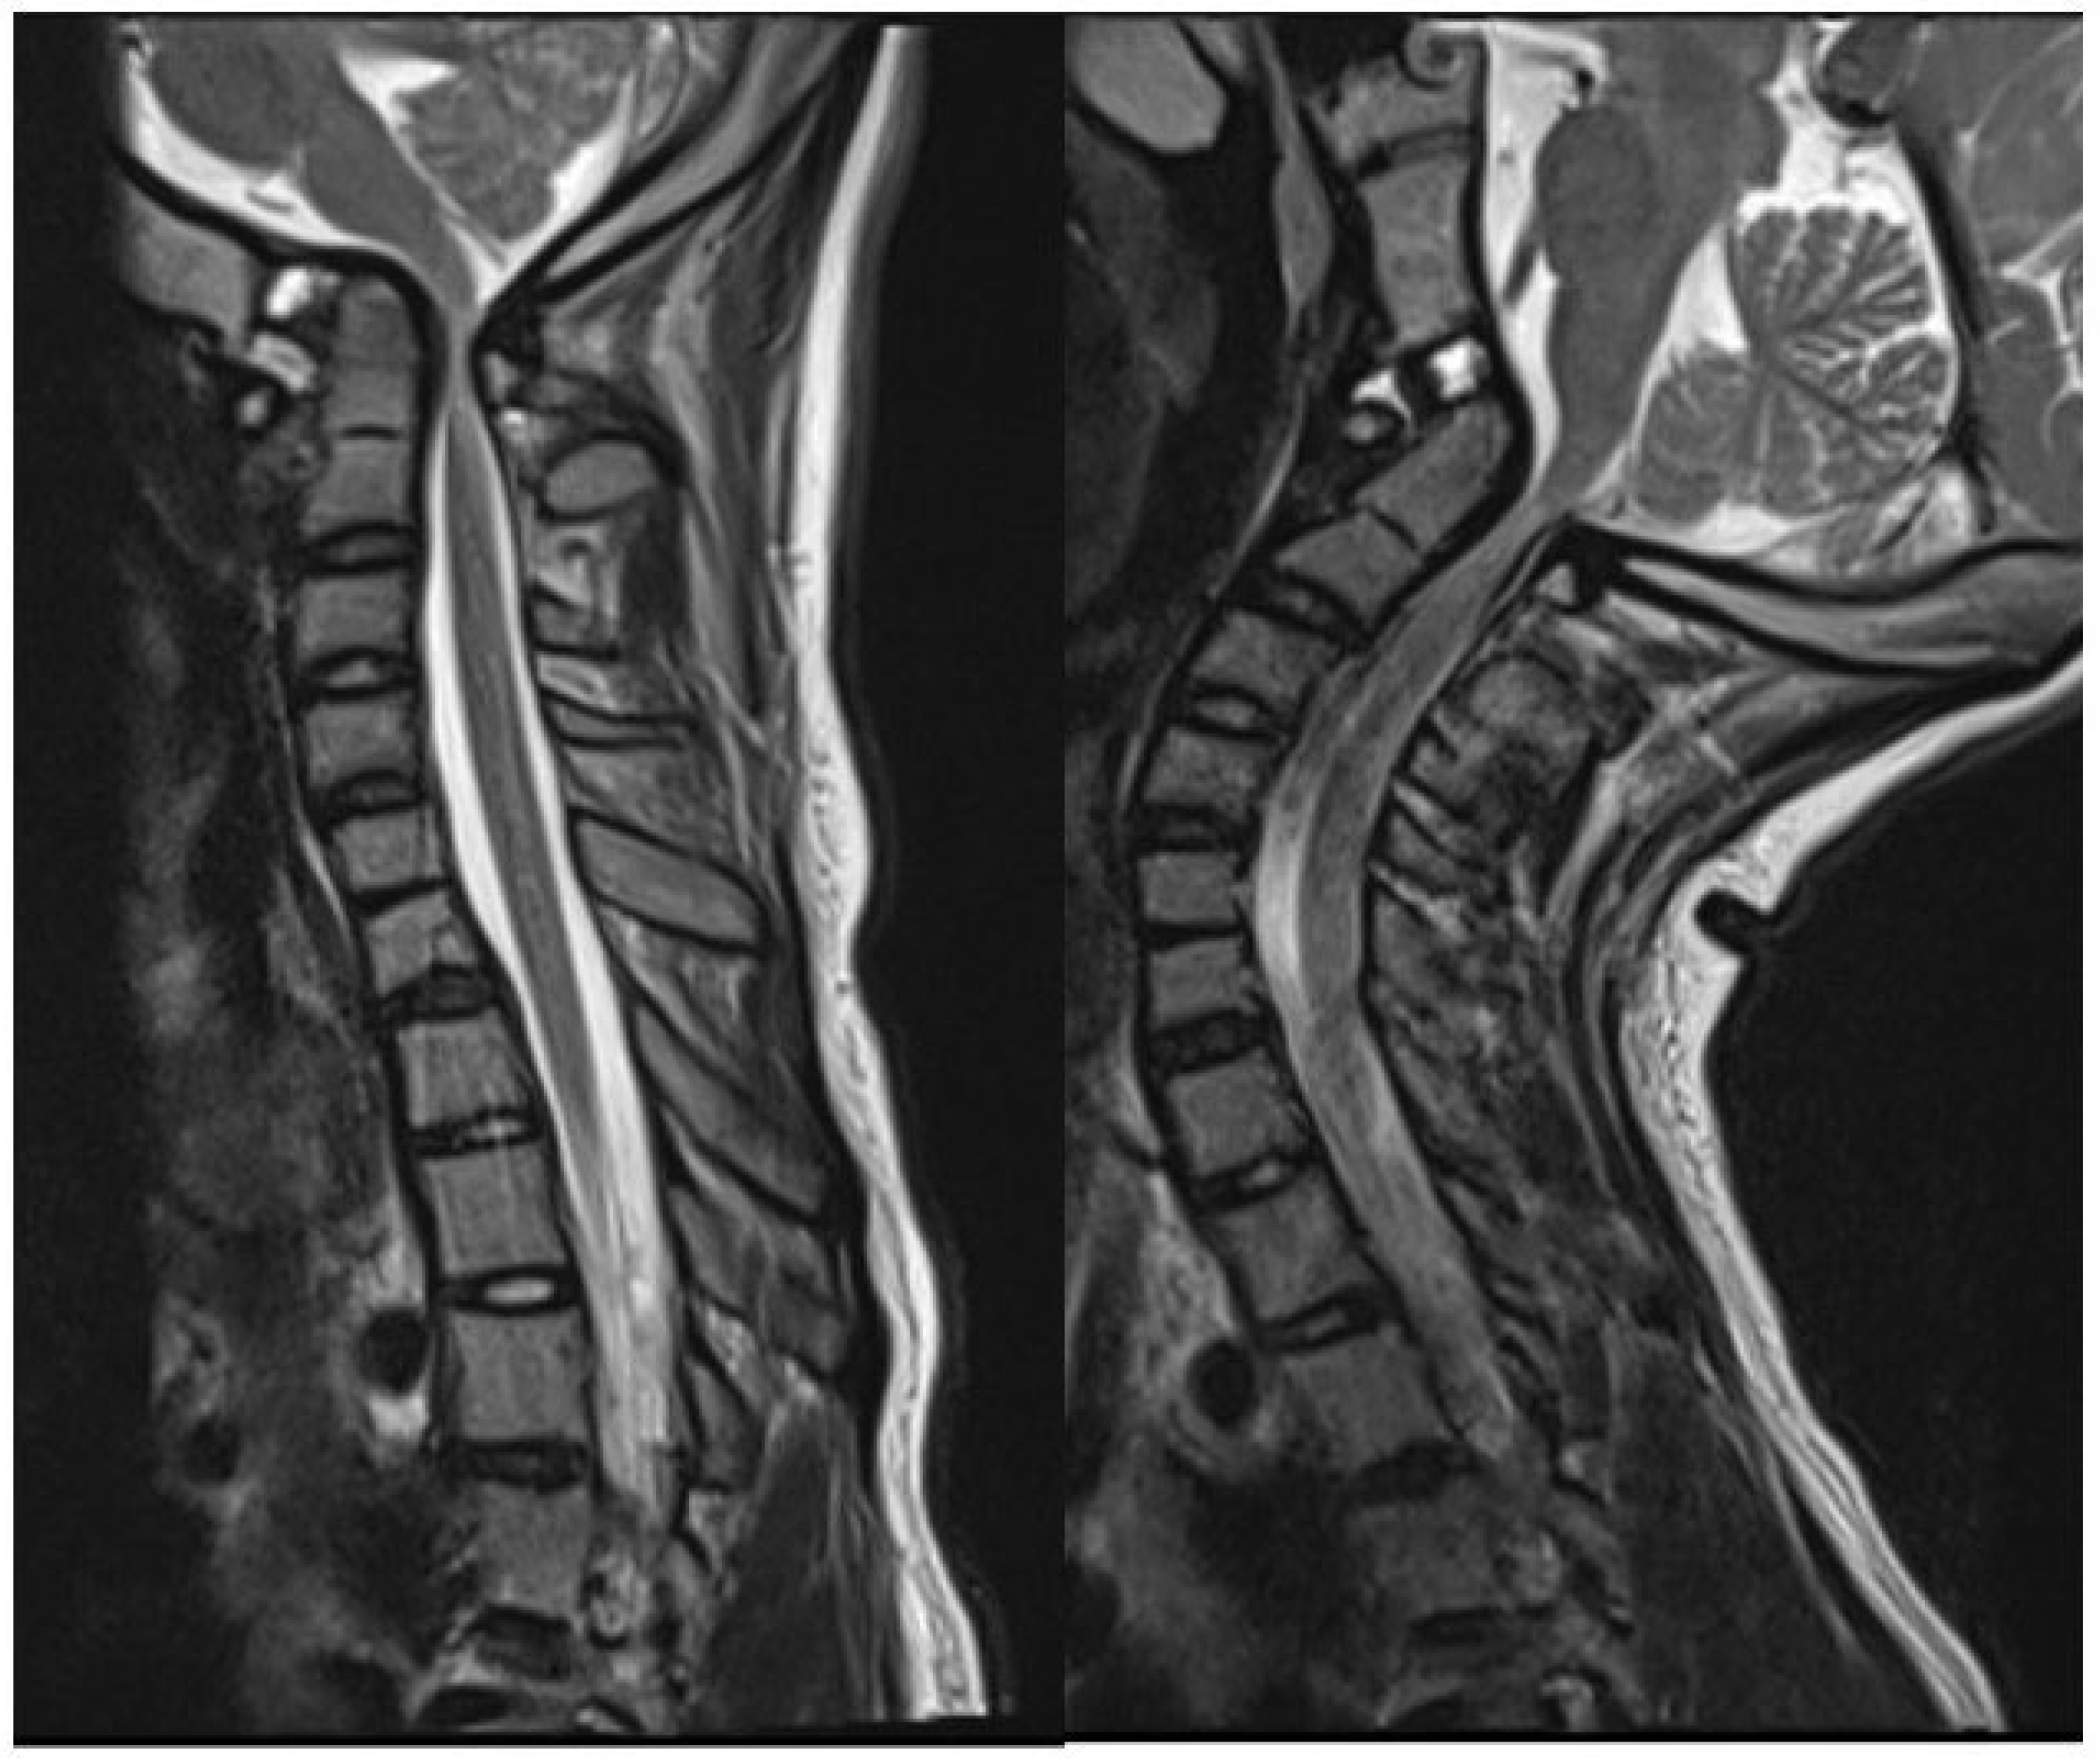

2.2. Imaging and Diagnosis